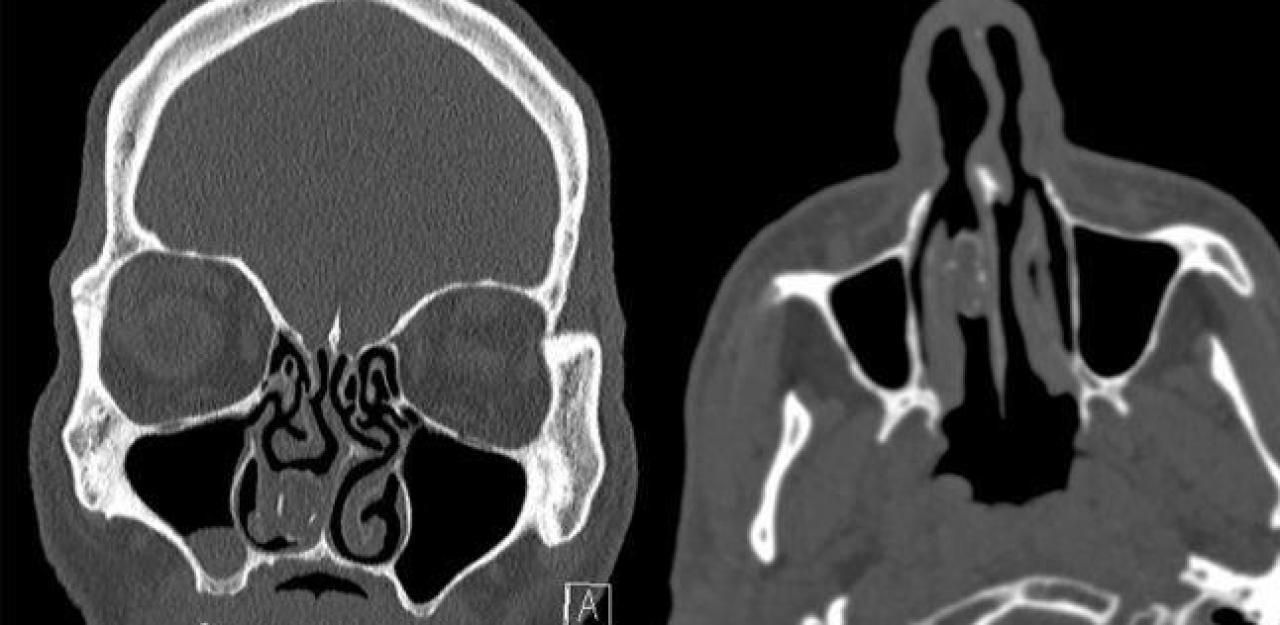

Nach 18 Jahren war aus dem Drogenpäckchen, das sich ein Australier in die Nase gesteckt hatte, ein Rhinolith, also ein Nasenstein geworden. Er ist auf dem CT-Scan im rechten Nasenloch (auf der Aufnahme links) zu sehen.

Bild: Smith et al., BMJ Case Reports, 2019